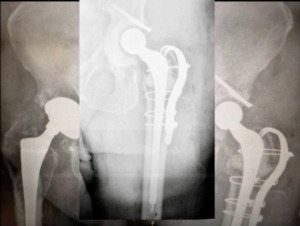

Also, I definitely like to avoid multiple implant representatives and companies, and in the OR, I like to stick with one. One of the problems I see is that there’s just so many people in the operating room. I have to “get 'em out of the way.” Actually, I can even operate on people. That’s important. That would be number six. Just to show you a case example this was a male patient came in with bilateral hip pain. (Figure 5)

His hips were done quite a while ago and recently, he had a coronary artery bypass. He’s got melanoma venous insufficiency. Just very exciting history. He’s pretty much a B bordering, not a C patient, but a definitely a B patient. We aspirated his right hip. It was negative, but the left hip unfortunately was positive on aspiration. He came back polymicrobial on next generation sequencing. But the only bug we came up with on culture was a corynebacterium. He had asymmetrical poly wear. We also did a metal ion workup through blood testing and he had really high metal ion levels. I was really concerned that he had worn through in an area and had metal ion activity. To look at it face value you’re prone to say, “okay, we can do that.” But things don’t always work out well.

But nevertheless I applied all these steps. All these pearls to get us to a point where we operated. The right hip was fine at least for right now. The left hip that’s infected. I suggested that we do a two-stage revision. The patient endorsed that. Why did we do it? The following is the report we received. (Figure 6)